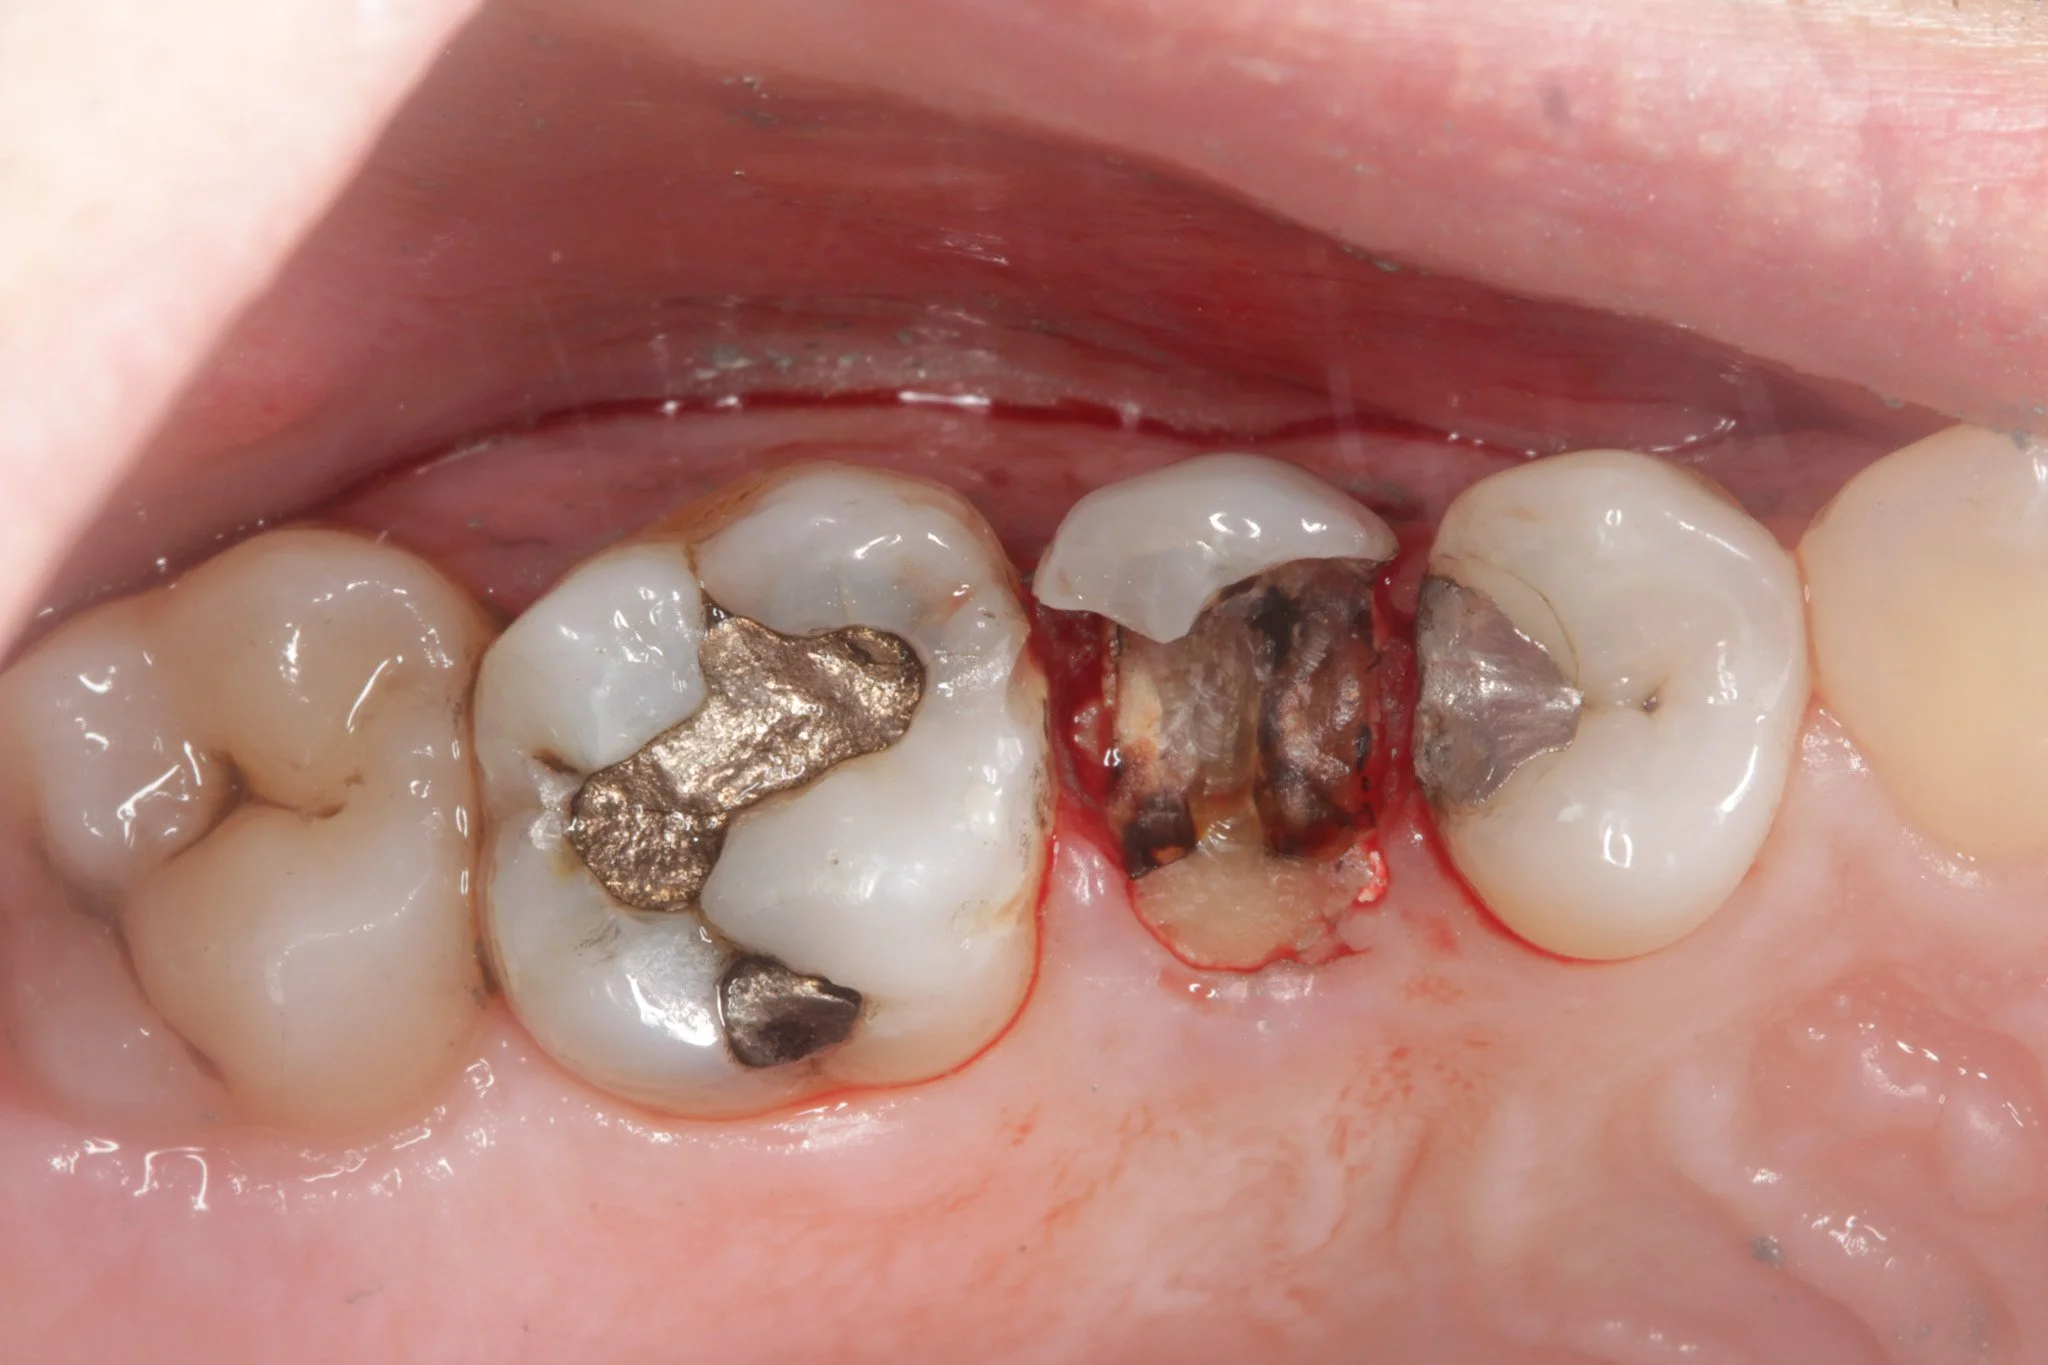

A deep metal dental filling

Removing the old filling and decay can cause irritation of the gums and bleeding

The margin of the filling here is stained and visible

Visible filling margins that have gathered a lot of staining